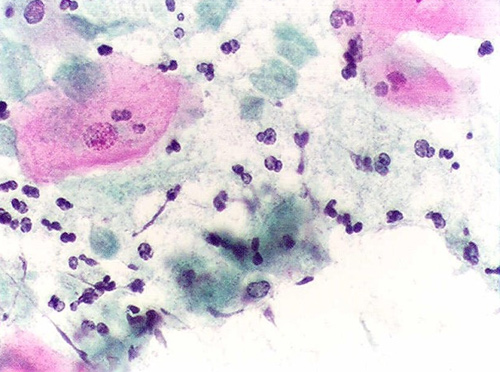

Nấm Candida là tác nhân phổ biến nhất gây viêm nhiễm phụ khoa

Tác nhân gây viêm phụ khoa chính là vi khuẩn, trùng roi và nấm. Trong môi trường thuận lợi các tác nhân này phát triển quá mức gây nên viêm nhiễm. Nguyên nhân dẫn đến sự phát triển quá mức của chúng bao gồm: